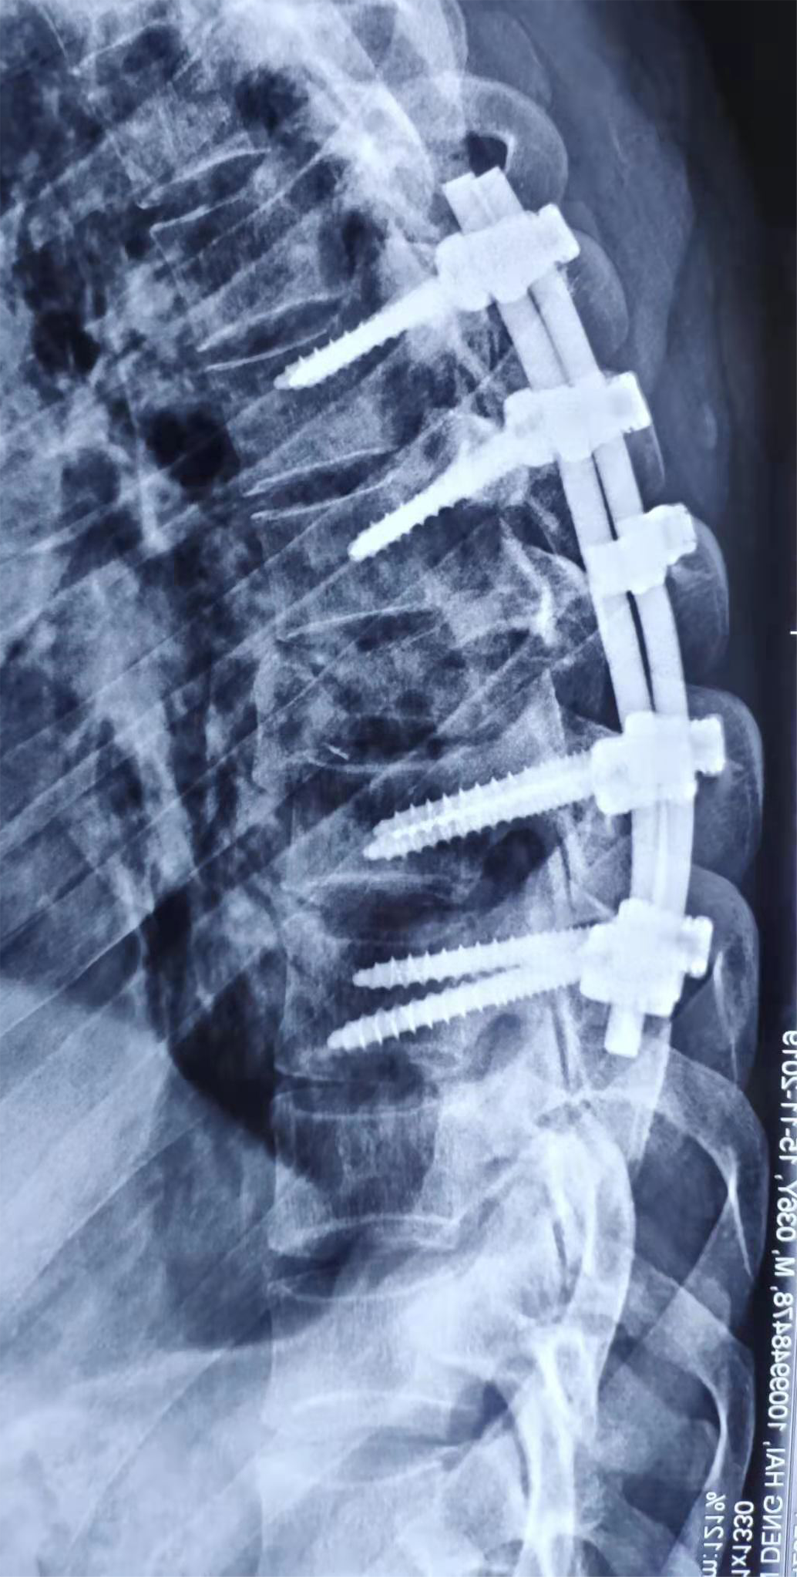

說起閆某的遭遇令人唏噓。他在礦井工作時,不幸被落下的碎石砸傷,導(dǎo)致胸椎、腰椎、肋骨、小腿多處骨折。由于病情危重從縣醫(yī)院轉(zhuǎn)往南京某醫(yī)院搶救,病情穩(wěn)定后經(jīng)歷了“后路胸椎骨折減壓復(fù)位植骨內(nèi)固定術(shù)”和“后路腰椎骨折切開減壓復(fù)位內(nèi)固定+左側(cè)腓骨骨折切開復(fù)位內(nèi)固定術(shù)”,身體里裝滿了螺釘鋼板。經(jīng)歷過生死考驗后,閆某第八胸椎以下感覺活動完全消失(雙下肢肌力0級,大小便失禁)。也就是醫(yī)學(xué)上說的“截癱”。閆某剛?cè)肟祻?fù)醫(yī)學(xué)科時,只能平躺,腰背部疼痛,雙下肢肌張力高,像“棍子”一樣僵直無法分開,輕輕觸碰就會抖動、痙攣。